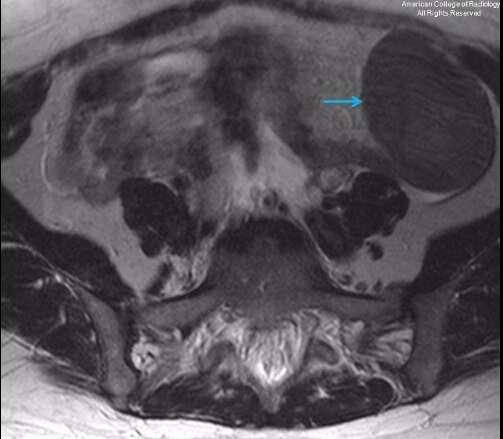

基本病史:患者女性,40 岁,腹痛,几年前曾做过子宫切除术。行腹部 CT 和 MR 检查,结果如下。![]() ![]() ![]() ![]() ![]() ![]() ![]() 诊断:弥漫性腹膜平滑肌瘤病 病例要点 弥漫性腹膜平滑肌瘤病是一种罕见的良性肿瘤,好发于育龄期女性,术前常误诊为子宫肌瘤,疾病受激素影响。 弥漫性腹膜平滑肌瘤在影像学上的特点,主要表现为腹膜或盆腔的小结节或大的实性软组织团块。鉴别诊断主要包括:腹膜转移癌,淋巴瘤,结核性腹膜炎,原发性腹膜间皮瘤,硬纤维瘤和平滑肌肉瘤。 MRI 可通过均匀对比度增强,显示与骨骼肌和平滑肌相似的信号强度,进而协助该病的诊断。 讨论 在腹膜上生长的众多平滑肌肿瘤中,弥漫性腹膜平滑肌溜病是其中一种罕见的良性肿瘤。好发于育龄期女性,其中又有很大一部分人合并子宫肌瘤切除术或子宫切除术。其他危险因素包括激素的影响,如妊娠,长期口服避孕药和卵巢颗粒细胞瘤。 腹膜转移癌是最令人重视的鉴别诊断。然而,转移癌的病人通常会体重下降和有腹水。肿瘤可以表现为浸润生长或是多发小结节,但是大的孤立性实性团块不常见。弥漫性腹膜平滑肌瘤病可以于无症状病人偶然发现,结节可大可小。全身症状不明显。原发性腹膜间皮瘤更常见于男性,常表现为腹膜内浸润的斑块和团块。 腹膜结核表现为低密度坏死结节灶。淋巴瘤表现为非坏死、非钙化的均质性腹膜后淋巴结肿大,通常不伴有明显的强化。平滑肌肉瘤有不典型增生,同时还有 FDG 摄取,在病理学上是恶性的。无法单独用影像学检查来区分平滑肌瘤为低度恶性还是良性。

MRI 见平滑肌瘤与骨骼肌和平滑肌有相似的 T1/T2 信号强度,并且静脉注射造影剂时同质强化。影像引导的经皮穿刺活检有助于诊断,但确诊需要剖腹探查和(或)组织检查明确病理为良性。治疗包括通过切除或非切除的手段移除所有的外源激素灶。因有罕见的肉瘤变可能,故需随访。 |